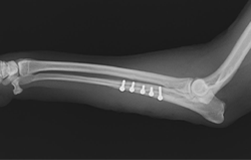

■ 症例2

極小犬(体重1.3㎏)の橈尺骨骨折

ロッキングプレート(TITAN LOCK)による固定